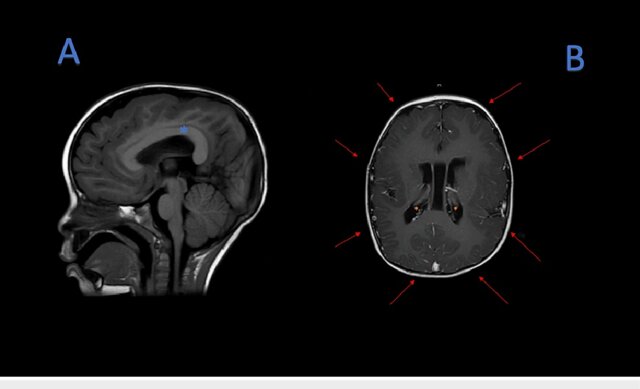

MRI T1 sequences

(A) MRI T1 sequence, thickening of the corpus callosum (blue asterisk). (B) MRI T1 sequence, pachygyria (red arrows), subependymal neuronal heterotopias (orange asterisk).